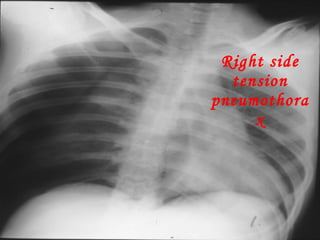

Right side tension pneumothorax

• #35 Here air has built up under pressure in the pleural space and collapsed the lung severely compromising ventilation. The pressure builds due to a ball valve type leak of air into the pleural space with air going into the space on each inspiration.